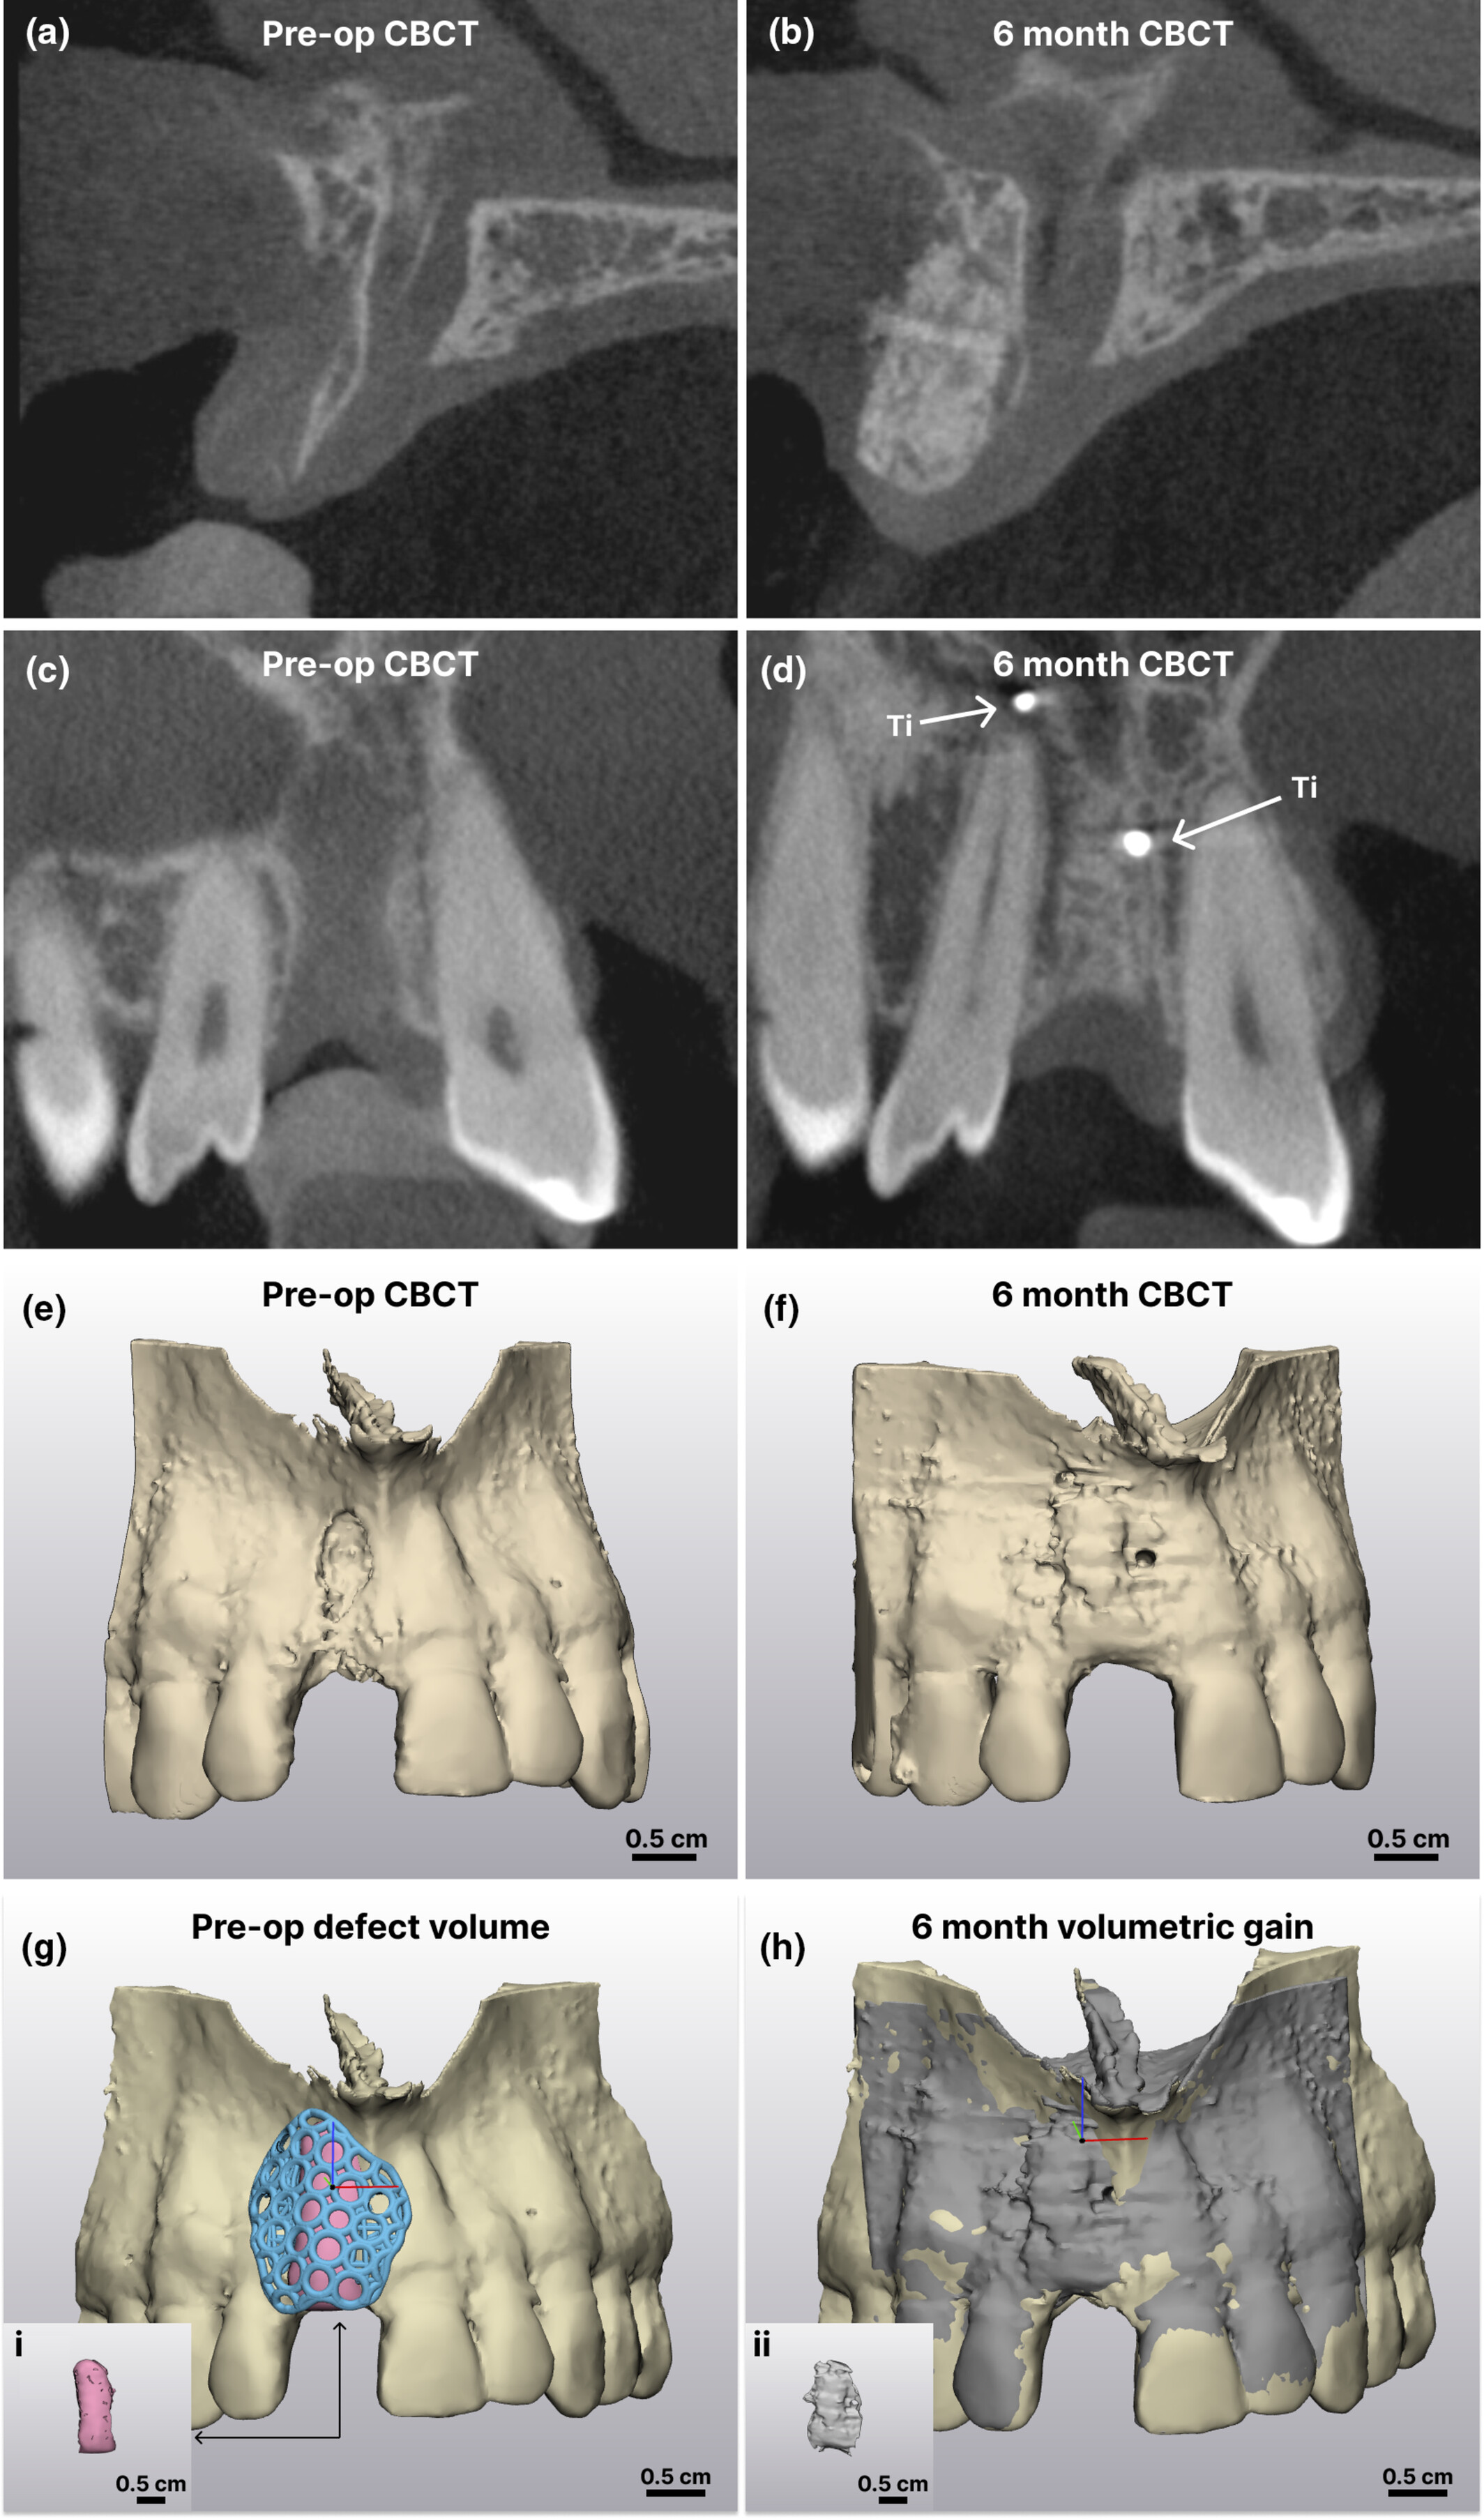

△案例中患者术前 GBR CBCT 与 6 个月愈合后的X 射线图像比较。 (a 和 c) 术前矢状面和冠状面横截面;(b 和 d) 术后 6 个月矢状面和冠状面横截面;(e 和 f) CBCT 图像的 3D 重建(术前和术后 6 个月);(g) 术前缺损体积;Ti,钛固定螺钉;(i) 粉色体积代表支架下方没有骨骼的区域;(h) 6 个月体积增加;(ii) 灰色体积的分割代表通过布尔减法得到的术前和 6 个月 CBCT 之间的差异。比例尺 = 0.5 cm。